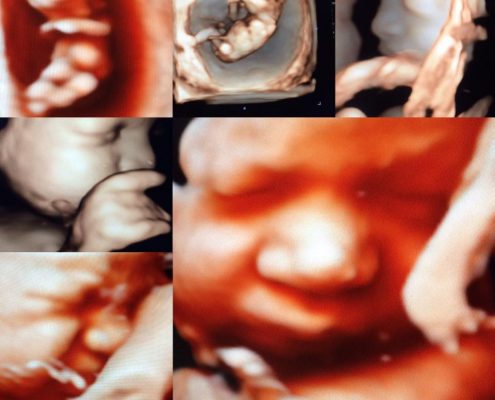

• Ultrason Görüntüleri

• Ultrason GörüntüleriEkim 1, 2014 - 16:34